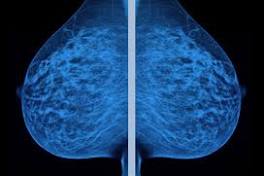

| Breast cancer diagnosis Grading breast cancer tissues using molecular portraits. ... Molecular serum portraits in patients with primary breast cancer predict the development of ...